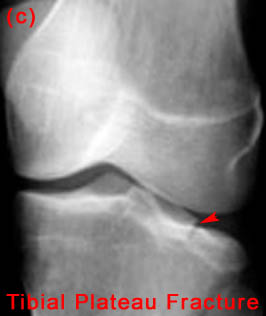

27) A patient is known to have a torn ACL and presents for x-ray examination of the knee. Which of the following abnormalities is often associated with a torn ACL?

"B&C" - Both Segond fractures and tibial plateau fractures are commonly associated with ACL tears.

28) Name the abnormality shown in the image below.

29) Give the specific name for the fracture type shown in the image above. Avulsion